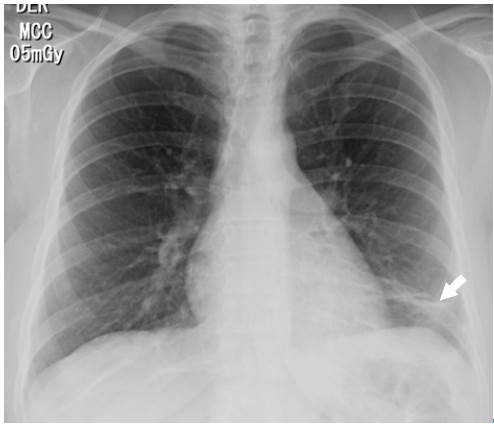

The following tests were performed: blood count, electrolytes, blood urea nitrogen (BUN) and creatinine, which were within normal limits. On the other hand, the electrocardiogram showed sinus tachycardia, while the echo-cardiogram had a structural and functionally normal heart. Finally, the chest X-ray revealed left basal lamellar atelectasis and right atrium growth (Figure 1).